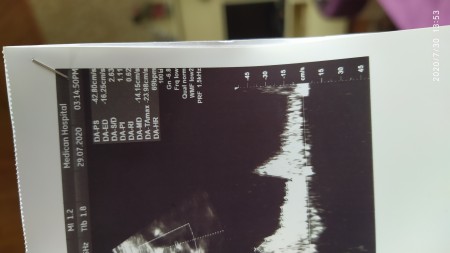

Dün detaylıya girdim, doktordan memnun kalmadım. Bebeğimin resmini bile doğru düzgün çekmedi :ermm: boyunu kilosunu da söylemedi. Bende o anki heycanla sormayı unuttum. Acaba burdan anlaşılır mı?

bu kalp atisi sadece canimm. Burda yazmaz

890grm 32.5 cmde boyu

Ac/bpd/fl falan yer var bu sekilde. Bak hemen onun karsisinda 890 yaziyor

görünmüyor Fl yazan yer boyu 7 ile çarp

Yaptım 32 çıktı, 26 haftaya göre normal mi canım?

güzel canm boyu